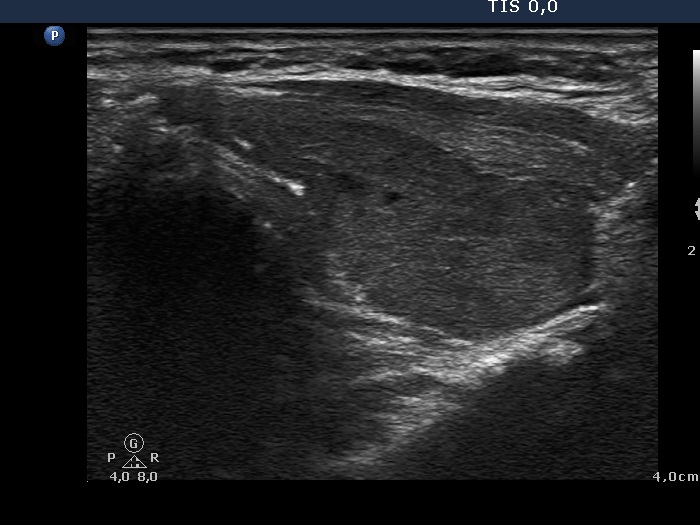

Clinical data: a 52-year-old hypothyroid woman was referred for an evaluation of a nodule detected by an ultrasound examination.

Ultrasonography: the thyroids were moderately hypoechogenic. The dorsal 4/5 of the left lobe was more hypoechogenic. This hypoechogenic area could be followed all along the dorsal part of the left lobe and the isthmus.

Comment: the shape of a nodule is egg- or ball-shaped. A pipe-shaped formation like a vessel or muscle fiber or as in this case a large area of the thyroid with different echo structures may mimic a nodule. But in the latter cases if we put the transducer in line with the formation we can notice the pipe-like shape. Conversely, if we put the transducer in other angles, first of all perpendicular to the object then it seems to be a nodule.